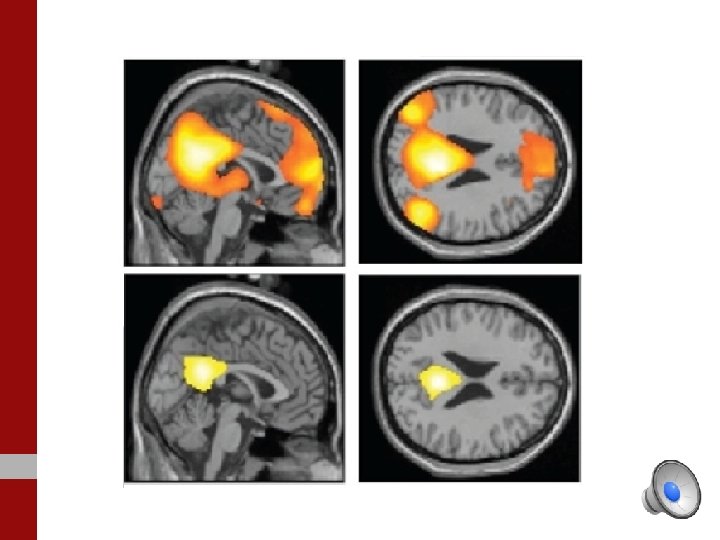

Un film d’horreur est montré à une personne contrôle

Le même film d’horreur est montré à une personnalité traumatique